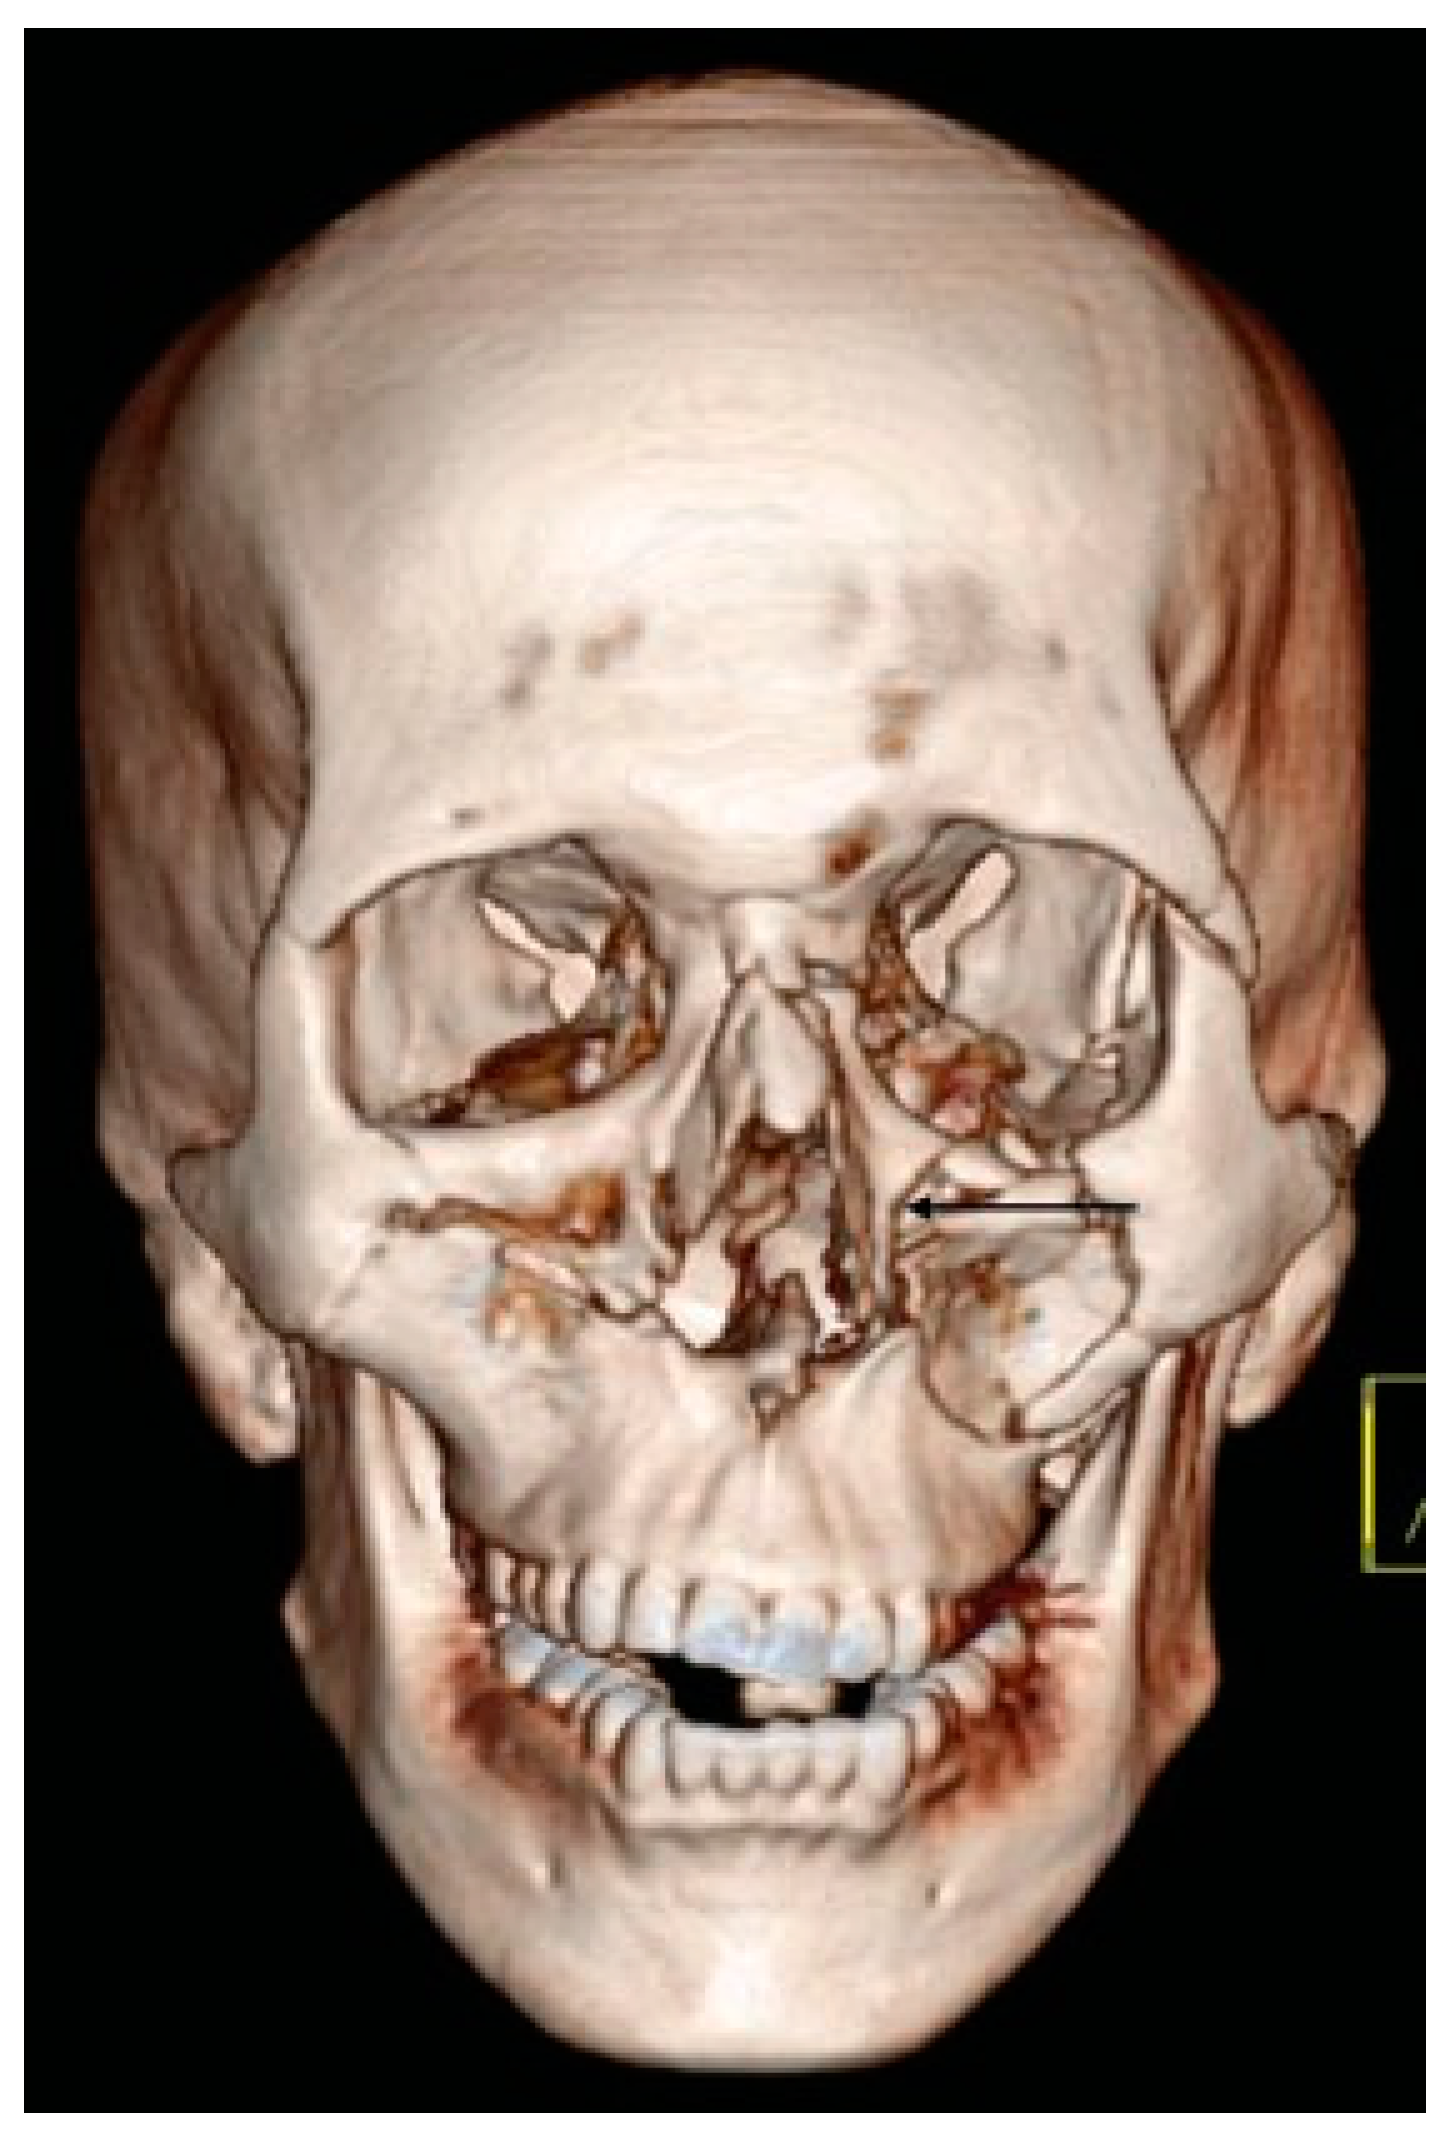

- Additional line extending from the pyriform aperture to the lateral wall of orbit, without breaking the infraorbital rim of the same side (5.4%).

- D3: Additional Line Extending from Pyriform Fossa to Lateral Wall of Orbit, without the Fracture of the Infraorbital Rim of the Same Side (5.4%)